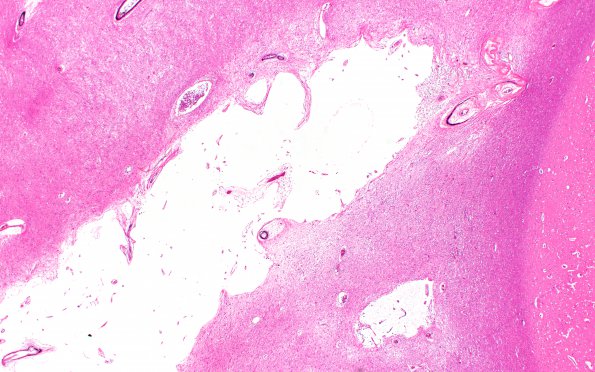

8B2 Dementia (Case 8) N11 H&E 2X

Higher magnification of image 8B1. (H&E)